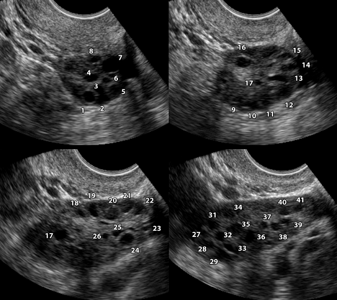

Поликистоз яичников виден при ультразвуковом исследовании, хотя и не всегда. У 20% женщин (не прошедших ещё через менопаузу), не имеющих симптомов поликистоза как такового, при ультразвуковом исследовании обнаруживают поликистозные яичники.

УЗИ помогает выявить следующие признаки заболевания:

СПКЯ обычно определяется как клинический синдром, вне зависимости от кистозных изменений яичников. Но присутствие в яичнике множества 2–6 мм или больших по размеру фолликулярных кист, содержащих атретичные клетки, является типичным. Яичники могут быть нормальных размеров или увеличены и иметь утолщенную и сглаженную белочную оболочку.

УЗИ органов малого таза

Более 10 фолликулов в каждом яичнике (выявленных при УЗИ тазовой полости), обычно раполагающихся по периферии и напоминающих нитку жемчуга

Трансвагинальное УЗИ может быть использовано для выявления аномалий в яичниках. Тем не менее, трансвагинальное УЗИ не проводится у девочек-подростков (см. ниже).

УЗИ органов малого таза обычно показано только в том случае, если уровень андрогенов в сыворотке или степень вирилизации указывают на наличие опухоли яичника. Трансвагинальная ультрасонография обычно не используется для диагностики СПКЯ у девочек-подростков, потому что она обнаруживает морфологию поликистоза у